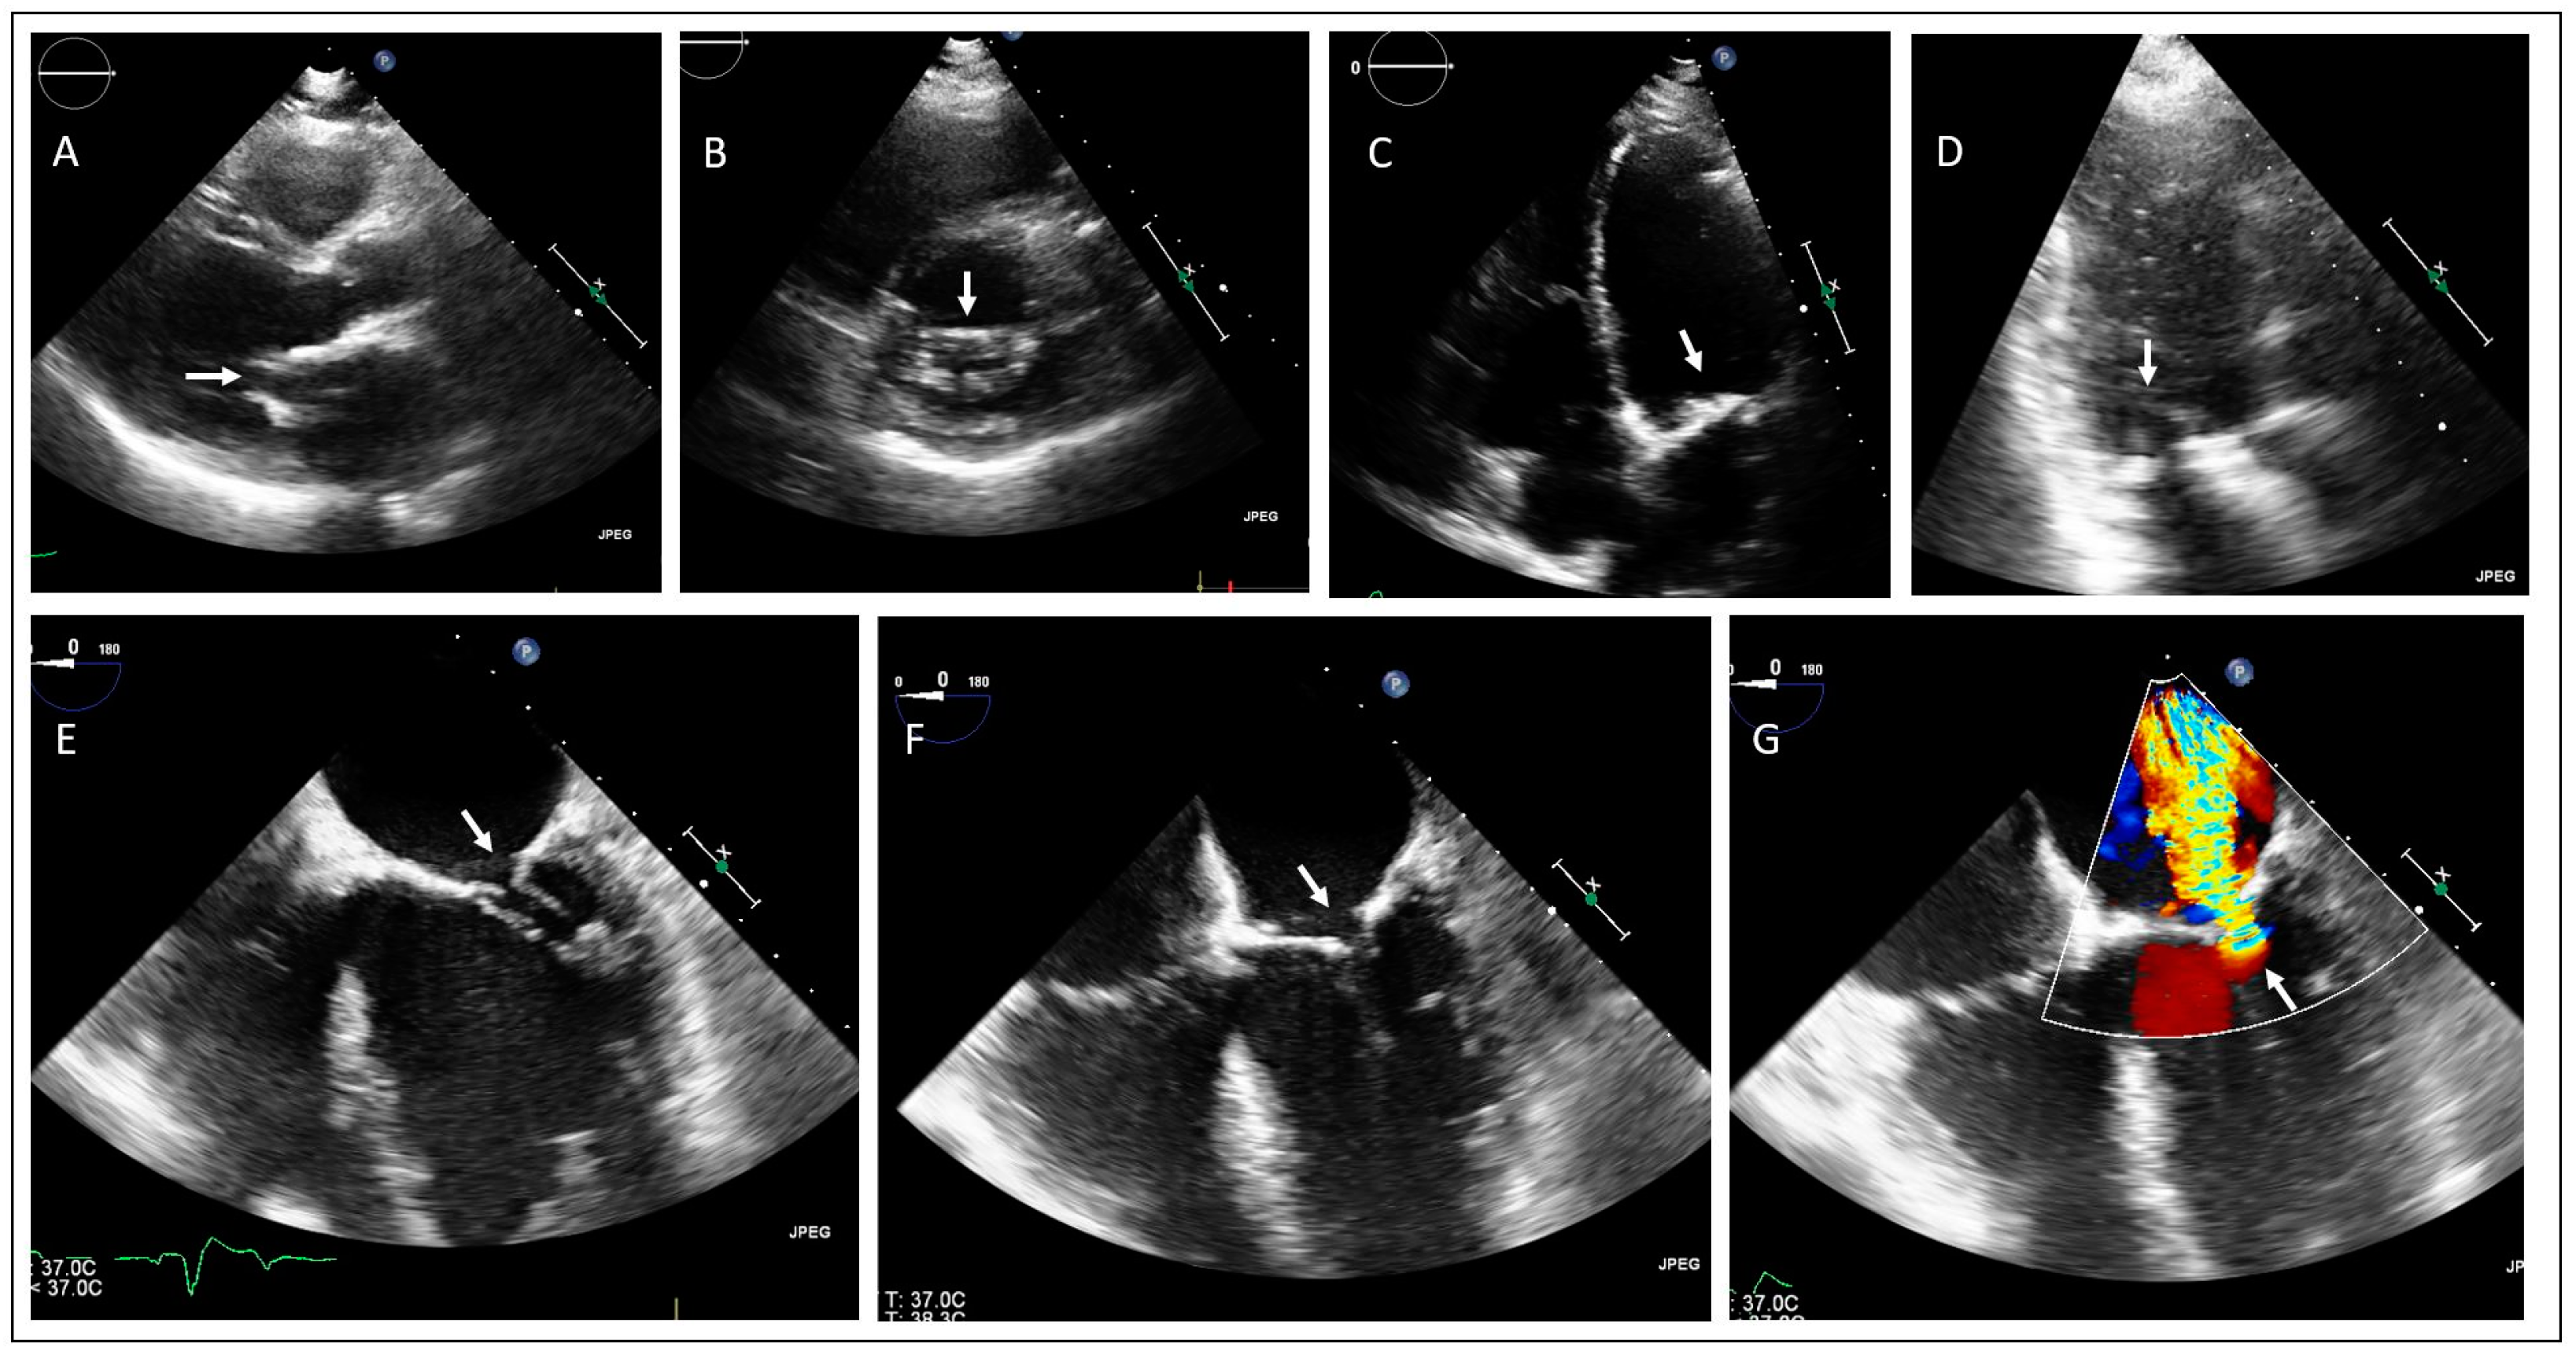

2. Case Presentations

2.1. Family 1

2.2. Family 2